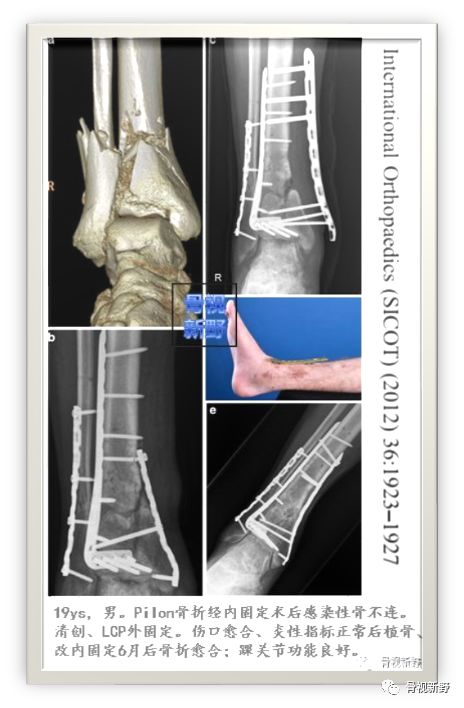

Pilon感染性骨不连LCP外固定

case